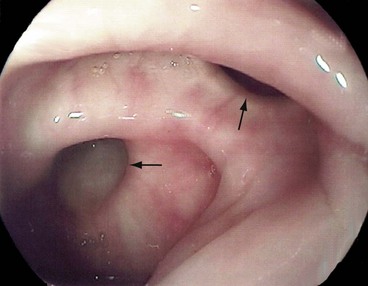

Colonic angiodysplasias have been recognised as a common cause of acute or chronic rectal bleeding and iron deficiency anaemia since the mid-1970s. The lesions are tiny hamartomatous vascular lesions in the colonic wall, usually in the ascending colon, and produce bleeding out of proportion to their size (see Fig. 29.8). They may also occur in the stomach and small bowel. The origin of colonic angiodysplasias is unknown but since they occur later in life, they are probably acquired and degenerative.

If bleeding is acute and is occurring rapidly, selective mesenteric arteriography may demonstrate the source of bleeding. In chronic or recurrent haemorrhage, large bowel lesions can be visualised by colonoscopy. This underlines the importance of thorough colonoscopy in patients with unexplained GI blood loss. Lesions can often be treated by electrical coagulation via a colonoscope. If unsuccessful, the affected segment is excised. Similar lesions occur more rarely in small bowel and bleed in the same way.